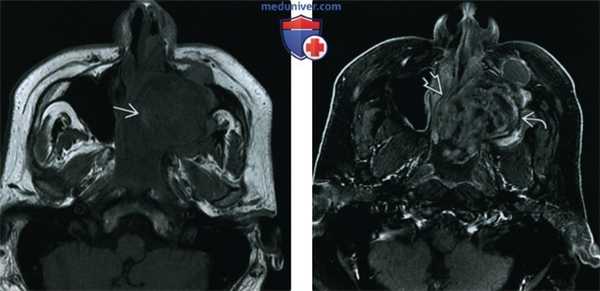

(Слева) При аксиальной МРТ Т2 FS визуализируется большое мукоцеле правой лобной пазухи с содержимым вариабельной интенсивности в нижних отделах. Мукоцеле распространяется в поверхностные мягкие ткани, приводя к их отеку.

(Справа) При аксиальной МРТ Т1 C+ FS у пациента с лобным мукоцеле: определяется отек и контрастное усиление поверхностных мягких тканей над разорвавшимся мукоцеле. Определяется также дуральное контрастирование передней черепной ямки, сопоставимое с ранним воспалением оболочек мозга.